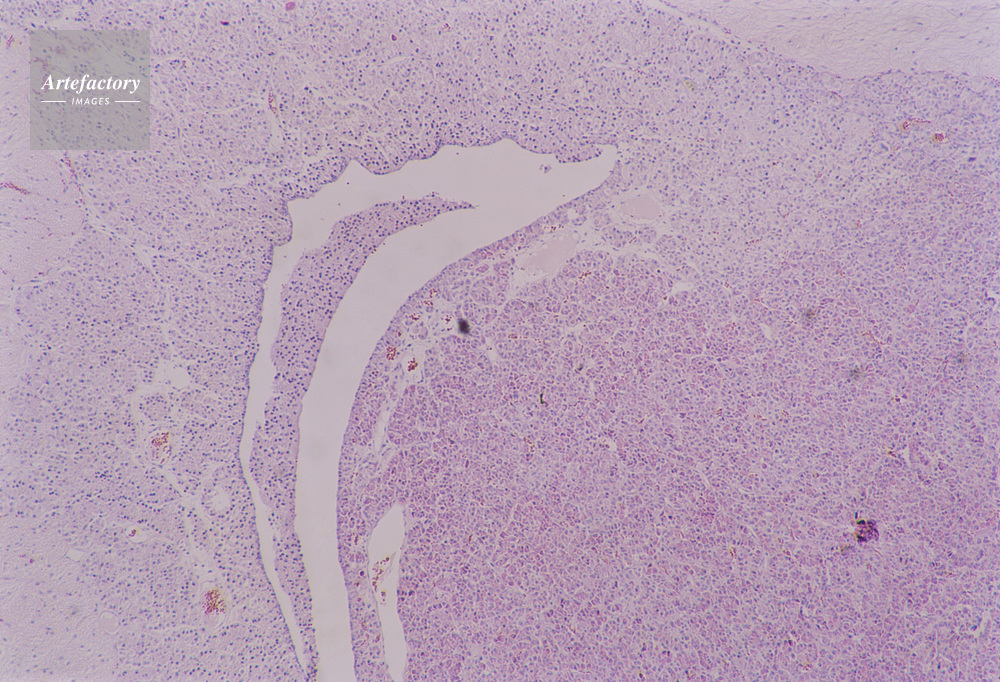

| キャプション | 脳下垂体,猿,40倍 | 制限事項 | ||

| ソース | ピクセル数 | 5544px × 3781px | ||